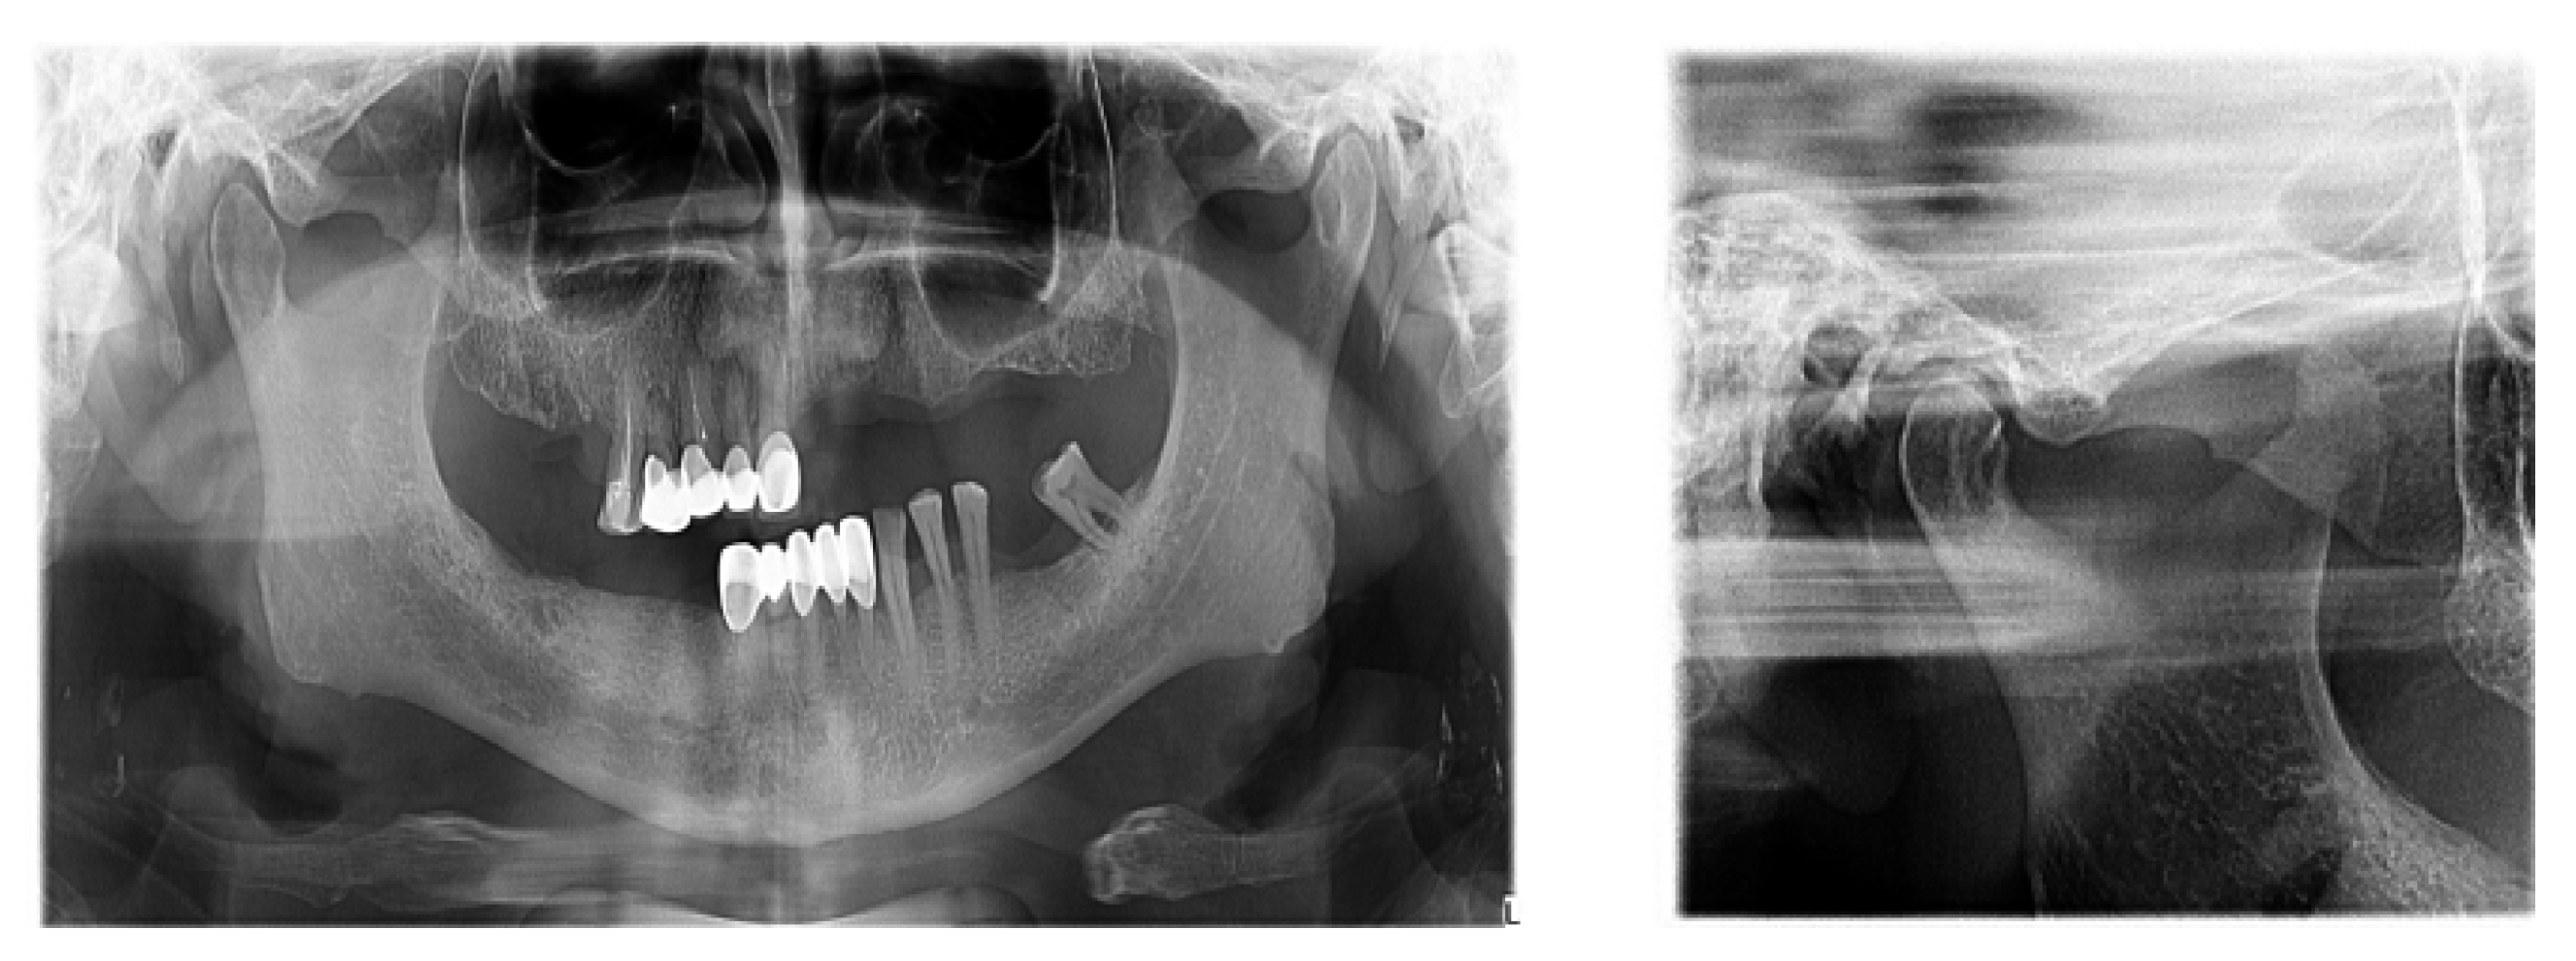

There is now good evidence that stress on the temporomandibular joints due to the absence of teeth in the posterior areas of the dental arches accentuates the signs and symptoms of dysfunction, but the causal link is not certain, in the sense that either dental occlusion causes the dysfunction or it results from the dysfunctional condition. The most recent evidence in the literature suggests that dental occlusion can be attributed to a secondary role in the onset of craniomandibular dysfunction, following trauma, oral parafunction, stress or dental iatrogenesis (Figure 5).

Figure 5.

TMJ tomography aspects in patients with periodontal injuries, open and shut position. (a) OPT with periodontal injuries; (b) TMJ aspect.

Regarding the paraclinical grounds, several sections detected on the CBCT, offering horizontal and vertical selective images with precision, are quite significant. The combination of the two observed resorptions is the basis for the clinical modifications induced by dental mobility. Thus, 25% of the study group followed the specialized imaging evaluations by bringing TMJ tomographs in the paraclinical register and the CBCT of TMJ.